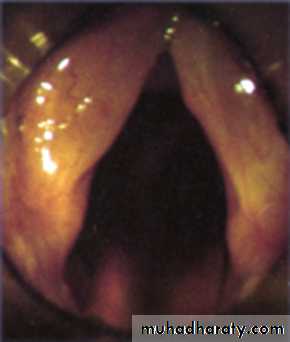

On examination: Indirect and fibroptic laryngoscopy reveals:

Redness and oedema of the larynx.

The vocal cords is covered with mucous and pus.

Indirect and fiberoptic laryngoscopy: Hyperaemia and oedema of the vocal cords. Excessive viscid secretions may be seen which results from increased activity of the mucous glands.